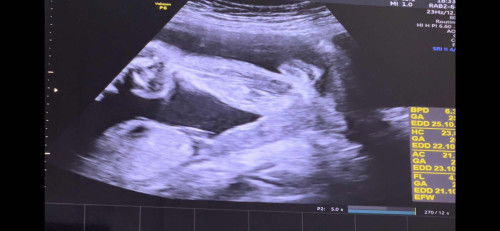

ผู้หญิง หรือผู้ชายคะแม่ๆ

แม่คนไหนมองออก ช่วยยืนยันให้ทีค่ะว่าน้องเป็น ญ หรือ ช #ขอความคิดเห็นของคุณแม่หน่อยค่ะ #ขอบคุณสำหรับคำคอมเม้นล่วงหน้าค่ะ #ขอบคุณล่วงหน้าสำหรับความคิดเห็นค่ะ